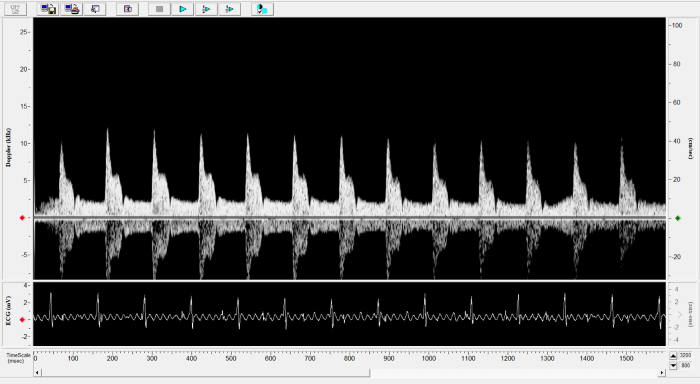

Carotid

Carotid Image. Image Credit: Scintica Instrumentation Inc.